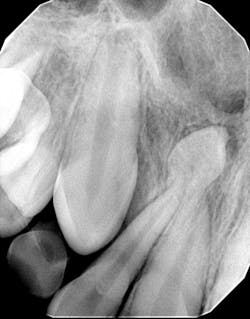

Diagnosis: Mesiodens tooth

For a recap on mesiodens teeth, diagnosis, and treatment, please refer to another case report I wrote that you might find of interest. Here is a quick- The lesions may occur “as single, multiple, unilateral, or bilateral (lesions); the presence of multiple supernumerary teeth is called ‘mesiodentes.’”1

- By way of appearance, they typically manifest in a conical- or peg-shaped form.2

- In general, supernumerary teeth—also referred to as hyperdontia or extra teeth—can occur in any location, but they are more prevalent in the maxilla (90%) as opposed to the mandible (10%).2

- The most common type of supernumerary teeth are mesiodentes.1 Their etiology remains unclear, although it is theorized that they are either an isolated finding or part of a “syndrome, specifically cleft lip and palate, cleidocranial dysostosis, and Gardner’s syndrome.”1

- Diagnosis is primarily via radiograph and can be confirmed by taking multiple angles using intraoral and extraoral radiographs (i.e., panoramic, periapicals, etc.). Furthermore, three-dimensional CBCT scans allow dialing in on the palatal location of the mesiodentes and their relationship to adjacent teeth. Delayed or altered eruptions of adult dentition also give rise to the suspicion of mesiodentes. Other common signs include cyst formation and crowding.

- Treatment of mesiodens varies. Although typically asymptomatic, they are “often extracted for aesthetic reasons, to allow the eruption of other teeth, orthodontic reasons, and/or suspected pathology.”3